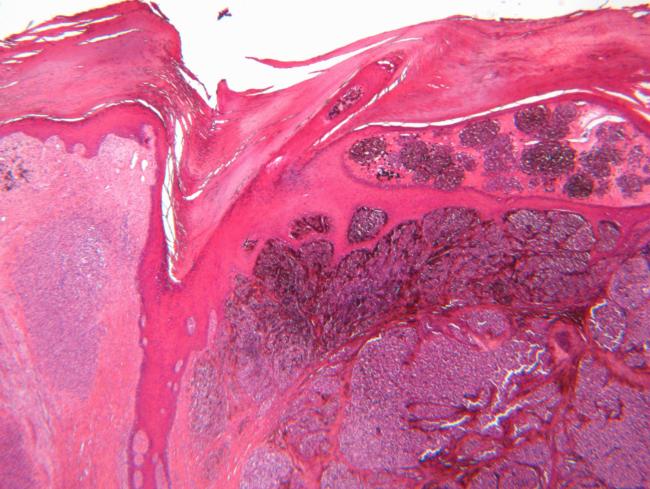

Researchers trained their model on single-cell datasets paired with survival data from hundreds of patients. They then tested it on clinical data from patients with melanoma or liver cancer and found it predicted outcomes more accurately than traditional methods.

The team also traced the model’s predictions back to specific cell groups, identifying immune and tumor cells linked to better or worse survival. In melanoma, they identified cell populations associated with responses to immunotherapy.